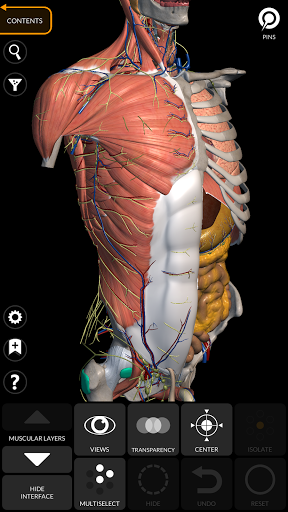

"Anatomía - Atlas 3D" permite estudiar la anatomía humana de forma fácil e interactiva.

A través de una interfaz sencilla e intuitiva es posible observar cada estructura anatómica desde cualquier ángulo.

Los modelos anatómicos 3D son especialmente detallados y con texturas de hasta una resolución de 4k.

La subdivisión por regiones y las vistas predefinidas facilitan la observación y el estudio de partes individuales o grupos de sistemas y las relaciones entre los diferentes órganos.

MODELOS ANATÓMICOS 3D

• Sistema musculoesquelético

nervioso • Sistema respiratorio • Sistema digestivo • Sistema urogenital (masculino y femenino) • Sistema endocrino • Sistema linfático • Sistema ocular y auditivo CARACTERÍSTICAS • Interfaz sencilla e intuitiva • Rotar y hacer zoom en cada modelo en el espacio 3D • Opción para ocultar o aislar uno o varios modelos seleccionados • Filtro para ocultar o mostrar cada sistema • Función de búsqueda para encontrar fácilmente cada parte anatómica • Función de marcador para guardar vistas personalizadas • Rotación inteligente que mueve el centro de rotación automáticamente • Función de transparencia • Visualización de músculos a través de niveles de capas desde las superficiales hasta las más profundas • Al seleccionar un modelo o un pin, aparece el término anatómico relacionado • Descripción de los músculos: origen, inserción, inervación y acción • Mostrar/ocultar interfaz de usuario (muy útil con pantallas pequeñas) MULTILINGÜE • Los términos anatómicos y la interfaz de usuario están disponibles en 11 idiomas: latín, inglés, francés, alemán, italiano, portugués, turco, ruso, español, Chino, japonés y coreano • Los términos anatómicos se pueden mostrar en dos idiomas simultáneamente REQUISITOS DEL SISTEMA • Android 8.0 o posterior, dispositivos con al menos 3 GB de RAM Reversi